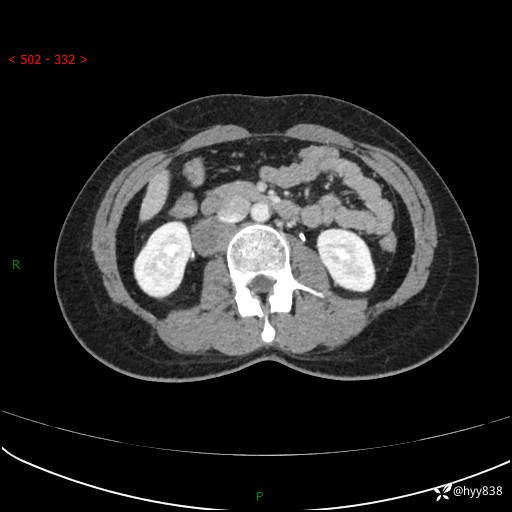

简要病史:患者于1天前因体检发现右旁肾占位,无肉眼血尿,无畏寒发热,无咳嗽咳痰,无腰腹部疼痛不适,无尿频尿急症状,起病来,患者未行特殊治疗,为求进一步诊治,门诊以"右侧腹膜后肿物"收治入院。 发病来患者精神、饮食、睡眠良好,小便如上,大便正常,体重无明显变化。

辅助检查:CT

临床诊断:腹膜后肿物

上腹部CT增强(动脉期+实质期)(外院平扫)